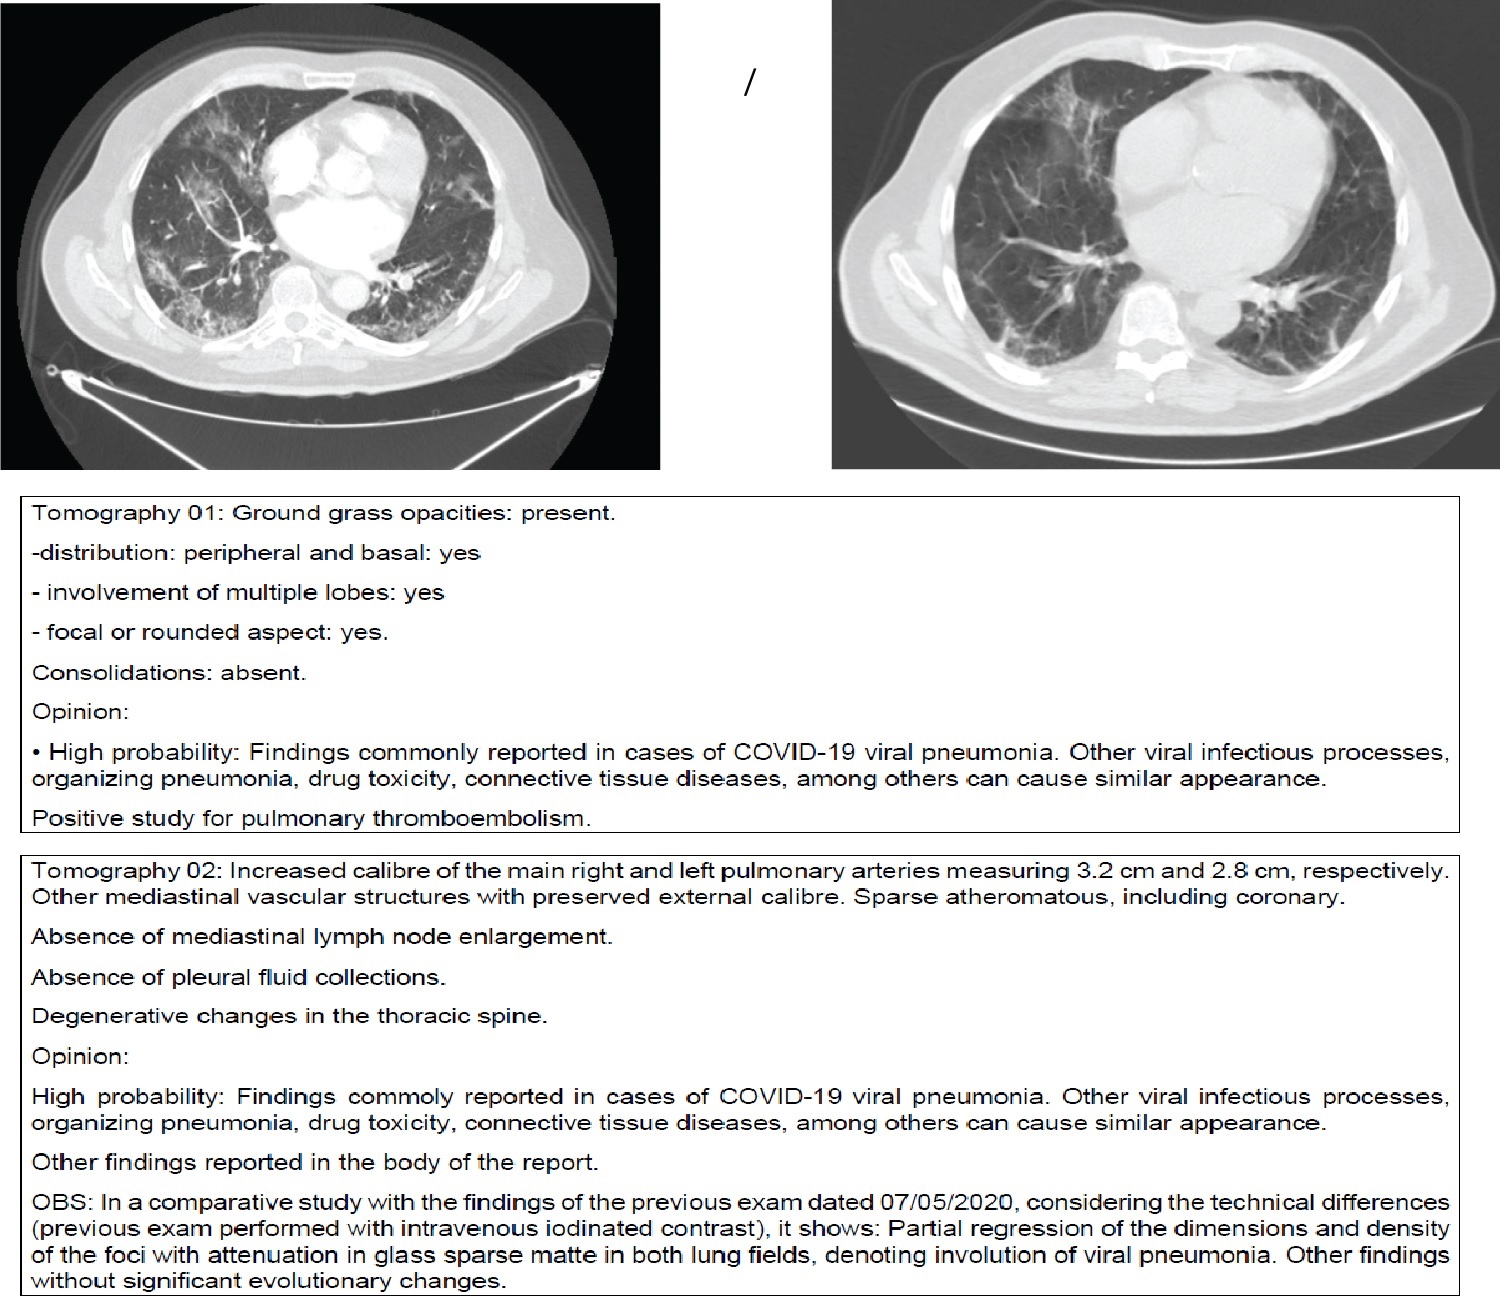

Figure 1: The pulse of Methylprednisolone in acute COVID-19. A 45-years-old man with previous obesity, hypertension and diabetes mellitus type II. He is admitted to E.R. after six days after that symptoms have started. Referred had a fever, myalgia, and malaise. He was pulsed with Methylprednisolone 1000 mg for- 3 days, beginning - on the first day of admission, due to higher ferritin levels. He was discharged after 8 days. Follow up was performed. He returned to outpatient follow-up with myalgia and malaise. Exams were showed no discrepancies, but the CBC hemogram showed mild leukopenia and ferritin level was below the average reference value. He was prescribed B complex vitamin for 1 month and Prednisolone 60 mg/day for 5 days followed by 20 mg for more 5 days. The patient had an excellent clinical response. New follow-up is going to happen soon. (CBC: Complete blood count). View Figure 1

Figure 2: The pulse of Methylprednisolone in chronic COVID-19. Patient, 68-years-old, previously admitted due to COVID-19.

After 7 days of hospital discharge, he had worsening effects in-breath and systemic symptoms such as fever and malaise. He was pulsed with Methylprednisolone 1g 3 days plus 5 days with 80 mg (first protocol). Exams not shown except for Urine with Enterococcus faecalis ampicillin SENSITIVE. He had improved and was discharged 1 day after the pulse (9 days after) with follow-up. A problem that is happening is recognizing these patients as being in the acute phase or community pneumonia. Acute phase has soft image at tomography, and chronic COVID-19 with worsening conditions in breath has more response to corticosteroids in low doses and less time of orotracheal intubation. View Figure 2

We have to keep in mind that we are still facing a war against an unknown virus. We are building knowledge and are now miles away from where we started. Standard lung images obtained when patients with systemic symptoms were readmitted (sometimes repeatedly) to Hospital showed acute Covid-19 mimicking findings. Some of those images are attached in Figures 6a-l.

Figure 6A-D: After ICU stay and orotracheal intubation and readmitted in the Infectious Diseases wards. Obese and or Diabetic patients after 14 days of disease. (14-40 days). Observe the "heavy" pattern of the images with opacities denoting extensive posterior atelectasis or even condensation in the pulmonary parenchyma in a diffuse manner. This tomography is different from the acute COVID-19 in Figure 1, where we have a ground grass pattern that is lighter and more tenuous. We are readmitting patients who already arrive with a "heavy" image pattern with new decompensation. This patient is not acute COVID-19; he is only exacerbating a disease, usually a vasculitis triggered by acute SARS-CoV-2 infection. In this phase, the patient responds better to corticosteroids and the intubation time is usually shorter since there is an evident autoimmune component. Differentiating between acute COVID-19 or COVID-19 in a critical phase (cHIS) is essential, as the pathophysiology of the disease changes: Acute COVID-19: viral action. Chronic COVID-19: Immunosuppression and autoimmunity phase. Two data are necessary to understand whether the case is acute or not: 1- To ask the patient whether he has had respiratory decompensations in the last months and what the recurrence is or whether there has been any change in his behaviour or pain, or tiredness in the last months - this can mean COVID-19 that has not been previously diagnosed; 2- Observing tomography: heavy hard images with laminar atelectasis and thickening of bronchi and bronchioles: Chronic phase; A lighter image of infiltration in frosted glass: acute COVID-19. The pattern of pneumonia after COVID-19 has been acute fibrinous and organizing pneumonia (AFOP) that is a histological pattern characterized predominantly by the presence of intra-alveolar fibrin in the form of fibrin "balls" within the alveolar spaces, with a patchy distribution, and organizing pneumonia. E-H: Patient, 46-years-old, HIV+ with viral load always undetectable and CD4+ always higher than 600, started skin lesions associated with pruritus without improvement. He mentions having seen three other doctors who considered Kaposi's Sarcoma hypothesis. However, when asked about his last semester, the patient reported an essential change in mood. I note that the lesions can be due to mastocytosis after COVID-19 or even vasculitis. We started Dexamethasone equivalent to a 250 mg dose of Methylprednisolone for 3 days and de-escalating the dose for another 5 days. It evolves on the first day with many tremors that improved after the second day. It also evolves with the improvement of skin lesions. I associated acetylsalicylic acid thinking about platelet activation in case of vasculitis and request new tests. I: Tomography shows ectasia of the ascending aorta, accentuation of the centrilobular stipple and presence of bronchial thickening; CD8 + = 270 and CD4 + = 197. Tomography findings appear in vasculitis and other diseases of the parenchyma. Possible diagnoses: Vasculitis, mastocytosis. The patient will be reassessed for new Cd4+ and CD8+ and skin biopsy collections if there are new lesions. J-L: Young, male, 19-years-old. Admitted to HSPE due to dyspnoea for more than 8 days. IgM and IgG positive. At the time, we questioned granulomatosis with polyangiitis, but we were surprised to see a positive sputum smear for Mycobacteria tuberculosis. Reanalysing, this case should be recalled and seen by a new aspect: COVID-19 + induced vasculitis + activation of latent tuberculosis by immunoparalysis. View Figure 6